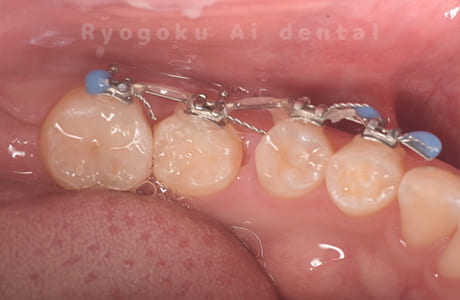

-

歯牙移植咬合面術前 -

移植する親知らず

歯牙移植術直後咬合面

歯牙移植術後咬合面

歯牙移植術前側面

歯牙移植術中側面

歯牙移植術後側面

部分矯正術前咬合面

部分矯正術中咬合面

部分矯正術後咬合面

部分矯正術前側面

部分矯正術中側面

部分矯正術後側面

- 原因

- 重度カリエス

- 治療内容

- 自家歯牙移植、部分矯正

- 治療費用

- 220,000円(移植費用)

110,000円(部分矯正費用)

虫歯が大きく、保存不可能となった歯を上の親知らずと交換する自家歯牙移植を行いました。移植歯が小ぶりであったため、部分矯正を行い問題なく噛み合い、経過良好です。